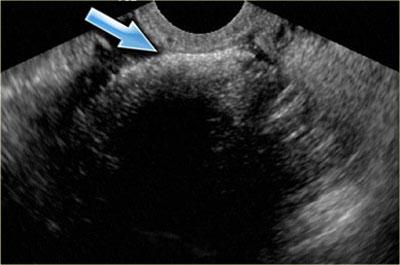

Siêu âm đường âm đạo cho thấy tổn thương dạng nang giảm âm kích thước lớn với các echo mức độ thấp lan tỏa

Lạc nội mạc tử cung dạng nang (Endometrioma)

Lạc nội mạc tử cung dạng nang (endometrioma) là loại nang hình thành khi mô nội mạc tử cung phát triển trong buồng trứng.

Bệnh ảnh hưởng đến phụ nữ trong độ tuổi sinh sản và có thể gây đau vùng chậu mạn tính liên quan đến chu kỳ kinh nguyệt.

Buồng trứng bị tổn thương ở khoảng 75% bệnh nhân mắc lạc nội mạc tử cung.

Trên siêu âm, hình ảnh endometrioma có thể đa dạng, nhưng đại đa số (khoảng 95%) bệnh nhân biểu hiện hình ảnh điển hình là nang đồng nhất, giảm âm với các echo mức độ thấp lan tỏa.

Hiếm gặp hơn, tổn thương có thể không có echo, dễ nhầm lẫn với nang buồng trứng chức năng.

Endometrioma có thể có nhiều ngăn và có các vách ngăn mỏng hoặc thậm chí dày.